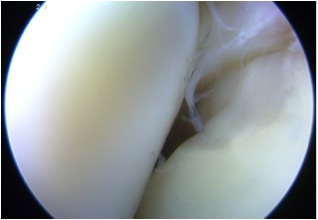

Arthroscopy

Chondral damage capitellum Chondral damage radial head Chondral damage ulnohumeral joint